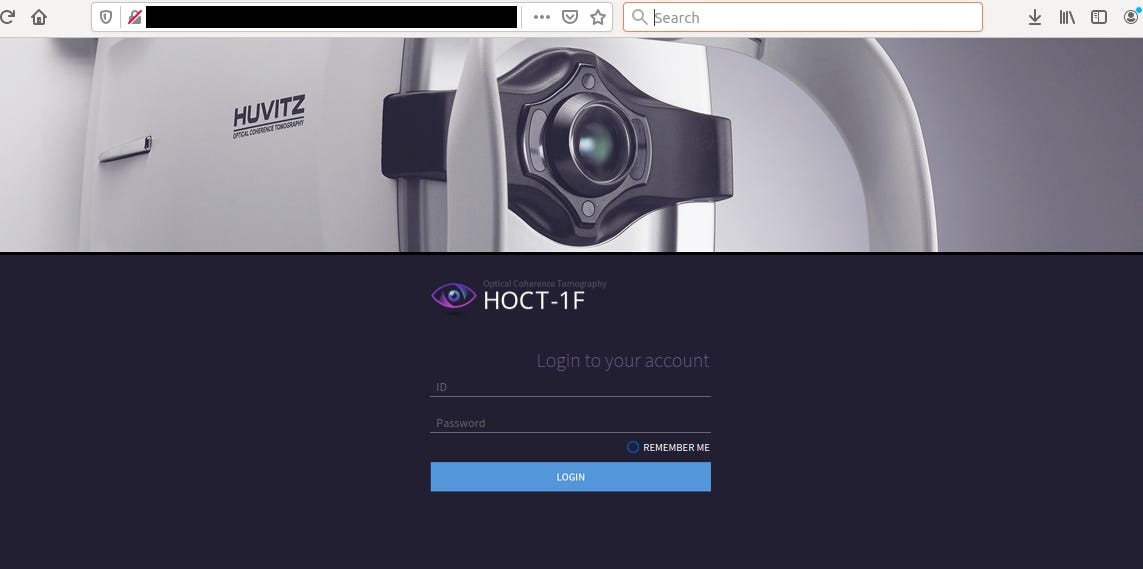

Bonus — Optical Coherence Tomography

Open Source Intelligence is not about knowing everything but about finding proper information and acquainted it as fast as possible to use it for specific purpose.

When you have no idea about device/software or any other finding, you should always depend on documentation that can be easily found from different sources.

It’s machine for optical coherence tomography and according to official site: Provides High-speed Scan, High-quality Image by using Huvitz’s outstanding optical technology and innovative image software. Shows extensive information, such as 3D structure of Retina, Macula’s thickness and separation, in a vivid image.

http://www.huvitz.com/oph_eng/product/HOCT-1.html

If you don’t know how to use this device or what kind of information it may contain, you need to find a manual guide.

It includes everything that you need to know about the device — from safety precautions, system overview or troubleshooting. Some of the manuals contains default password and installation guide as well.